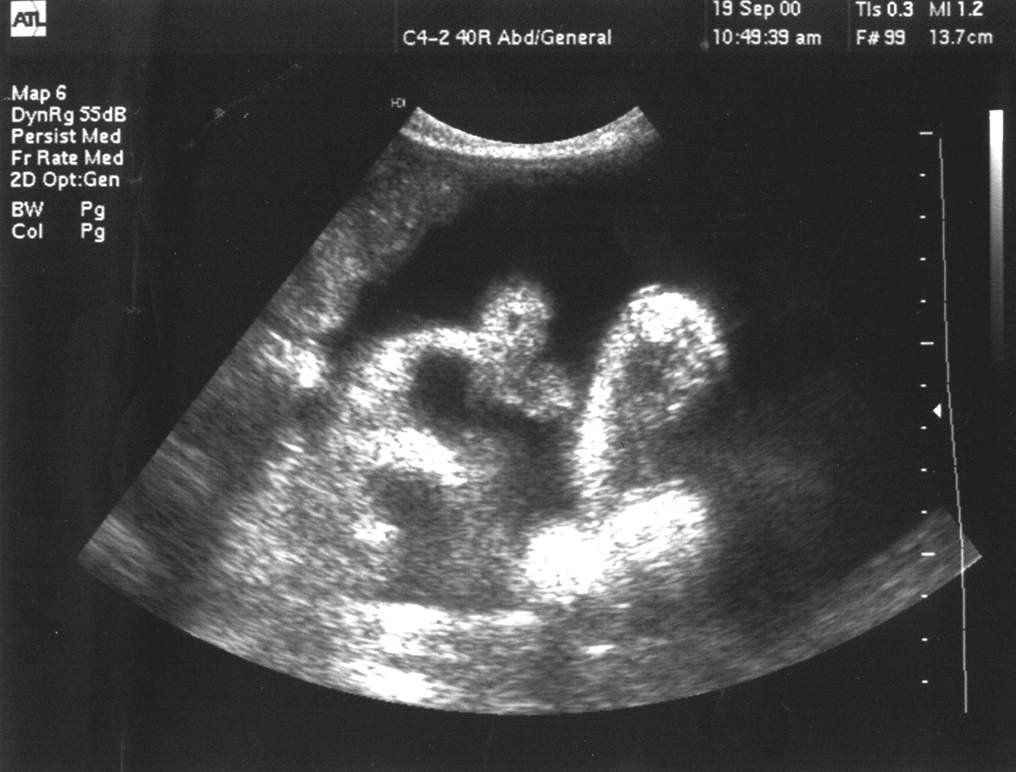

2、肝脏实质内回声:呈现网格状回声增强区,增强光带将肝实质分隔成<3cm的小区,小区形态不规则,内部回声不均匀。

3、肝硬化表现

4、脾大较显著